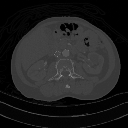

Three-dimensional visualization techniques are used to integrate a series of tomographic slices into a form which is often easier to interpret than the slices on their own. An overview of the major visualization techniques used in medical imaging is presented in this chapter. We'll start with the integration of two-dimensional (2D) axial images before considering various three-dimensional (3D) image presentation methods.

The following set of images will be used to help us with our task. They consist of a SPECT lung-ventilation study, illustrated by the animated sequence on the left, a SPECT lung-perfusion study, in the middle, and a CT pulmonary angiogram (CTPA) from the same patient on the right:

We'll use these image sets at various stages in this chapter so as to provide examples which will help with demonstrating the essence of the techniques we'll consider. Acquisition factors for the image sets include 128 x 128 pixel slices each of thickness 4.8 mm for the SPECT studies and 512 x 512 pixel contiguous slices of thickness 1.5 mm for the axial images reconstructed from the CTPA helical scan. In addition, the lung-perfusion scan was acquired immediately following the ventilation scan, so that residual activity from the latter is present in the former at a level of about 20%.